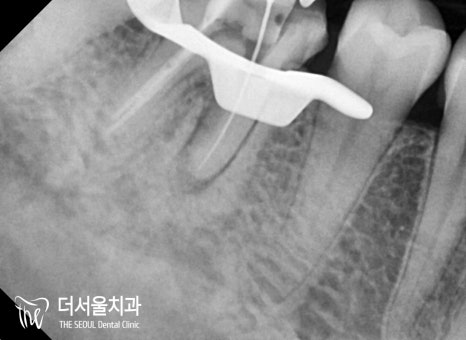

치근단 방사선으로 확인해 본

오른쪽은 뿌리가 갈라지는

분지부부터 앞쪽 뿌리 주변이

검게 변해 있는 것을 볼 수 있습니다.

또한 이전에 진료를 받았다는 것을

채워진 근관 내 충전재를 통해 알 수 있었죠.